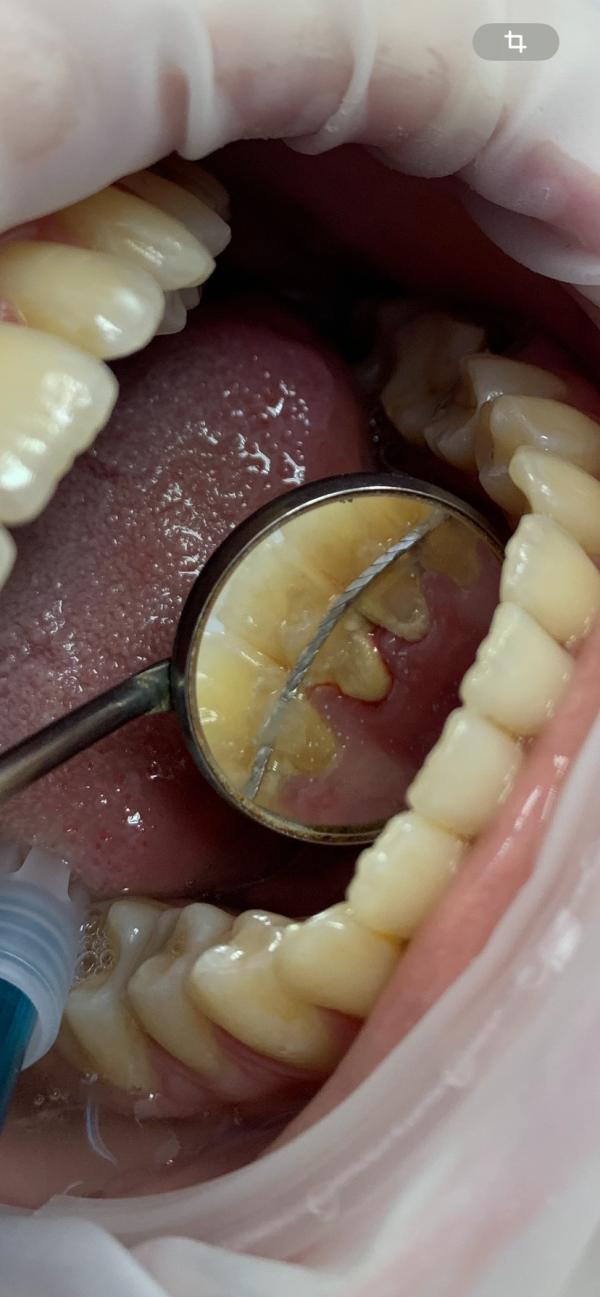

Профессиональная чистка Зубов 2500₽🩵

Запись по номеру 89886486800💁🏻‍♀️📱